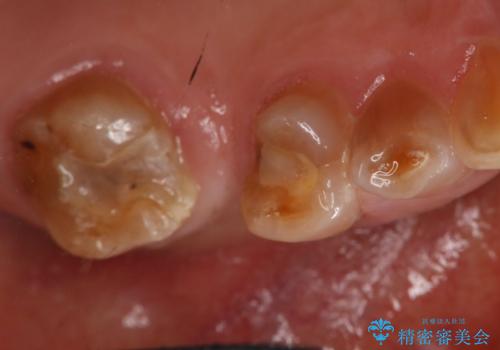

- 左上臼歯部に保険のブリッジを入れていたがすぐに取れてしまったので自費治療でのやり変えを希望された患者様です。

インプラントとブリッジを提案しましたが時間をかけたくないとのことだったので、ブリッジでの治療を選択しました。

左上6番が大きく傾いているため、露髄や痛みが出る可能性を事前にお伝えしています。